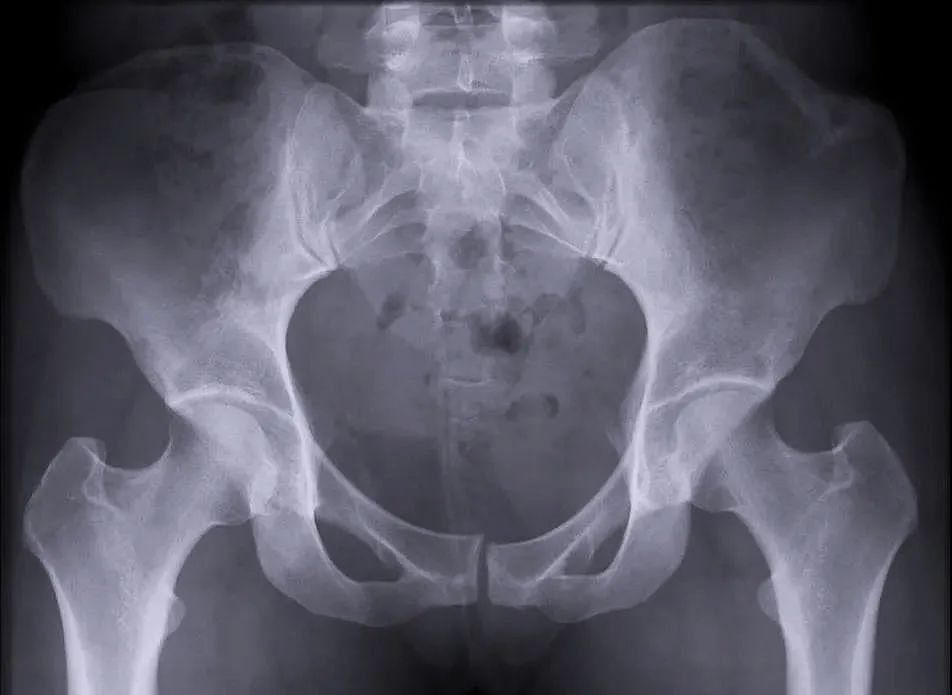

【醫療科普】:外傷性骨折影像

外傷性骨折